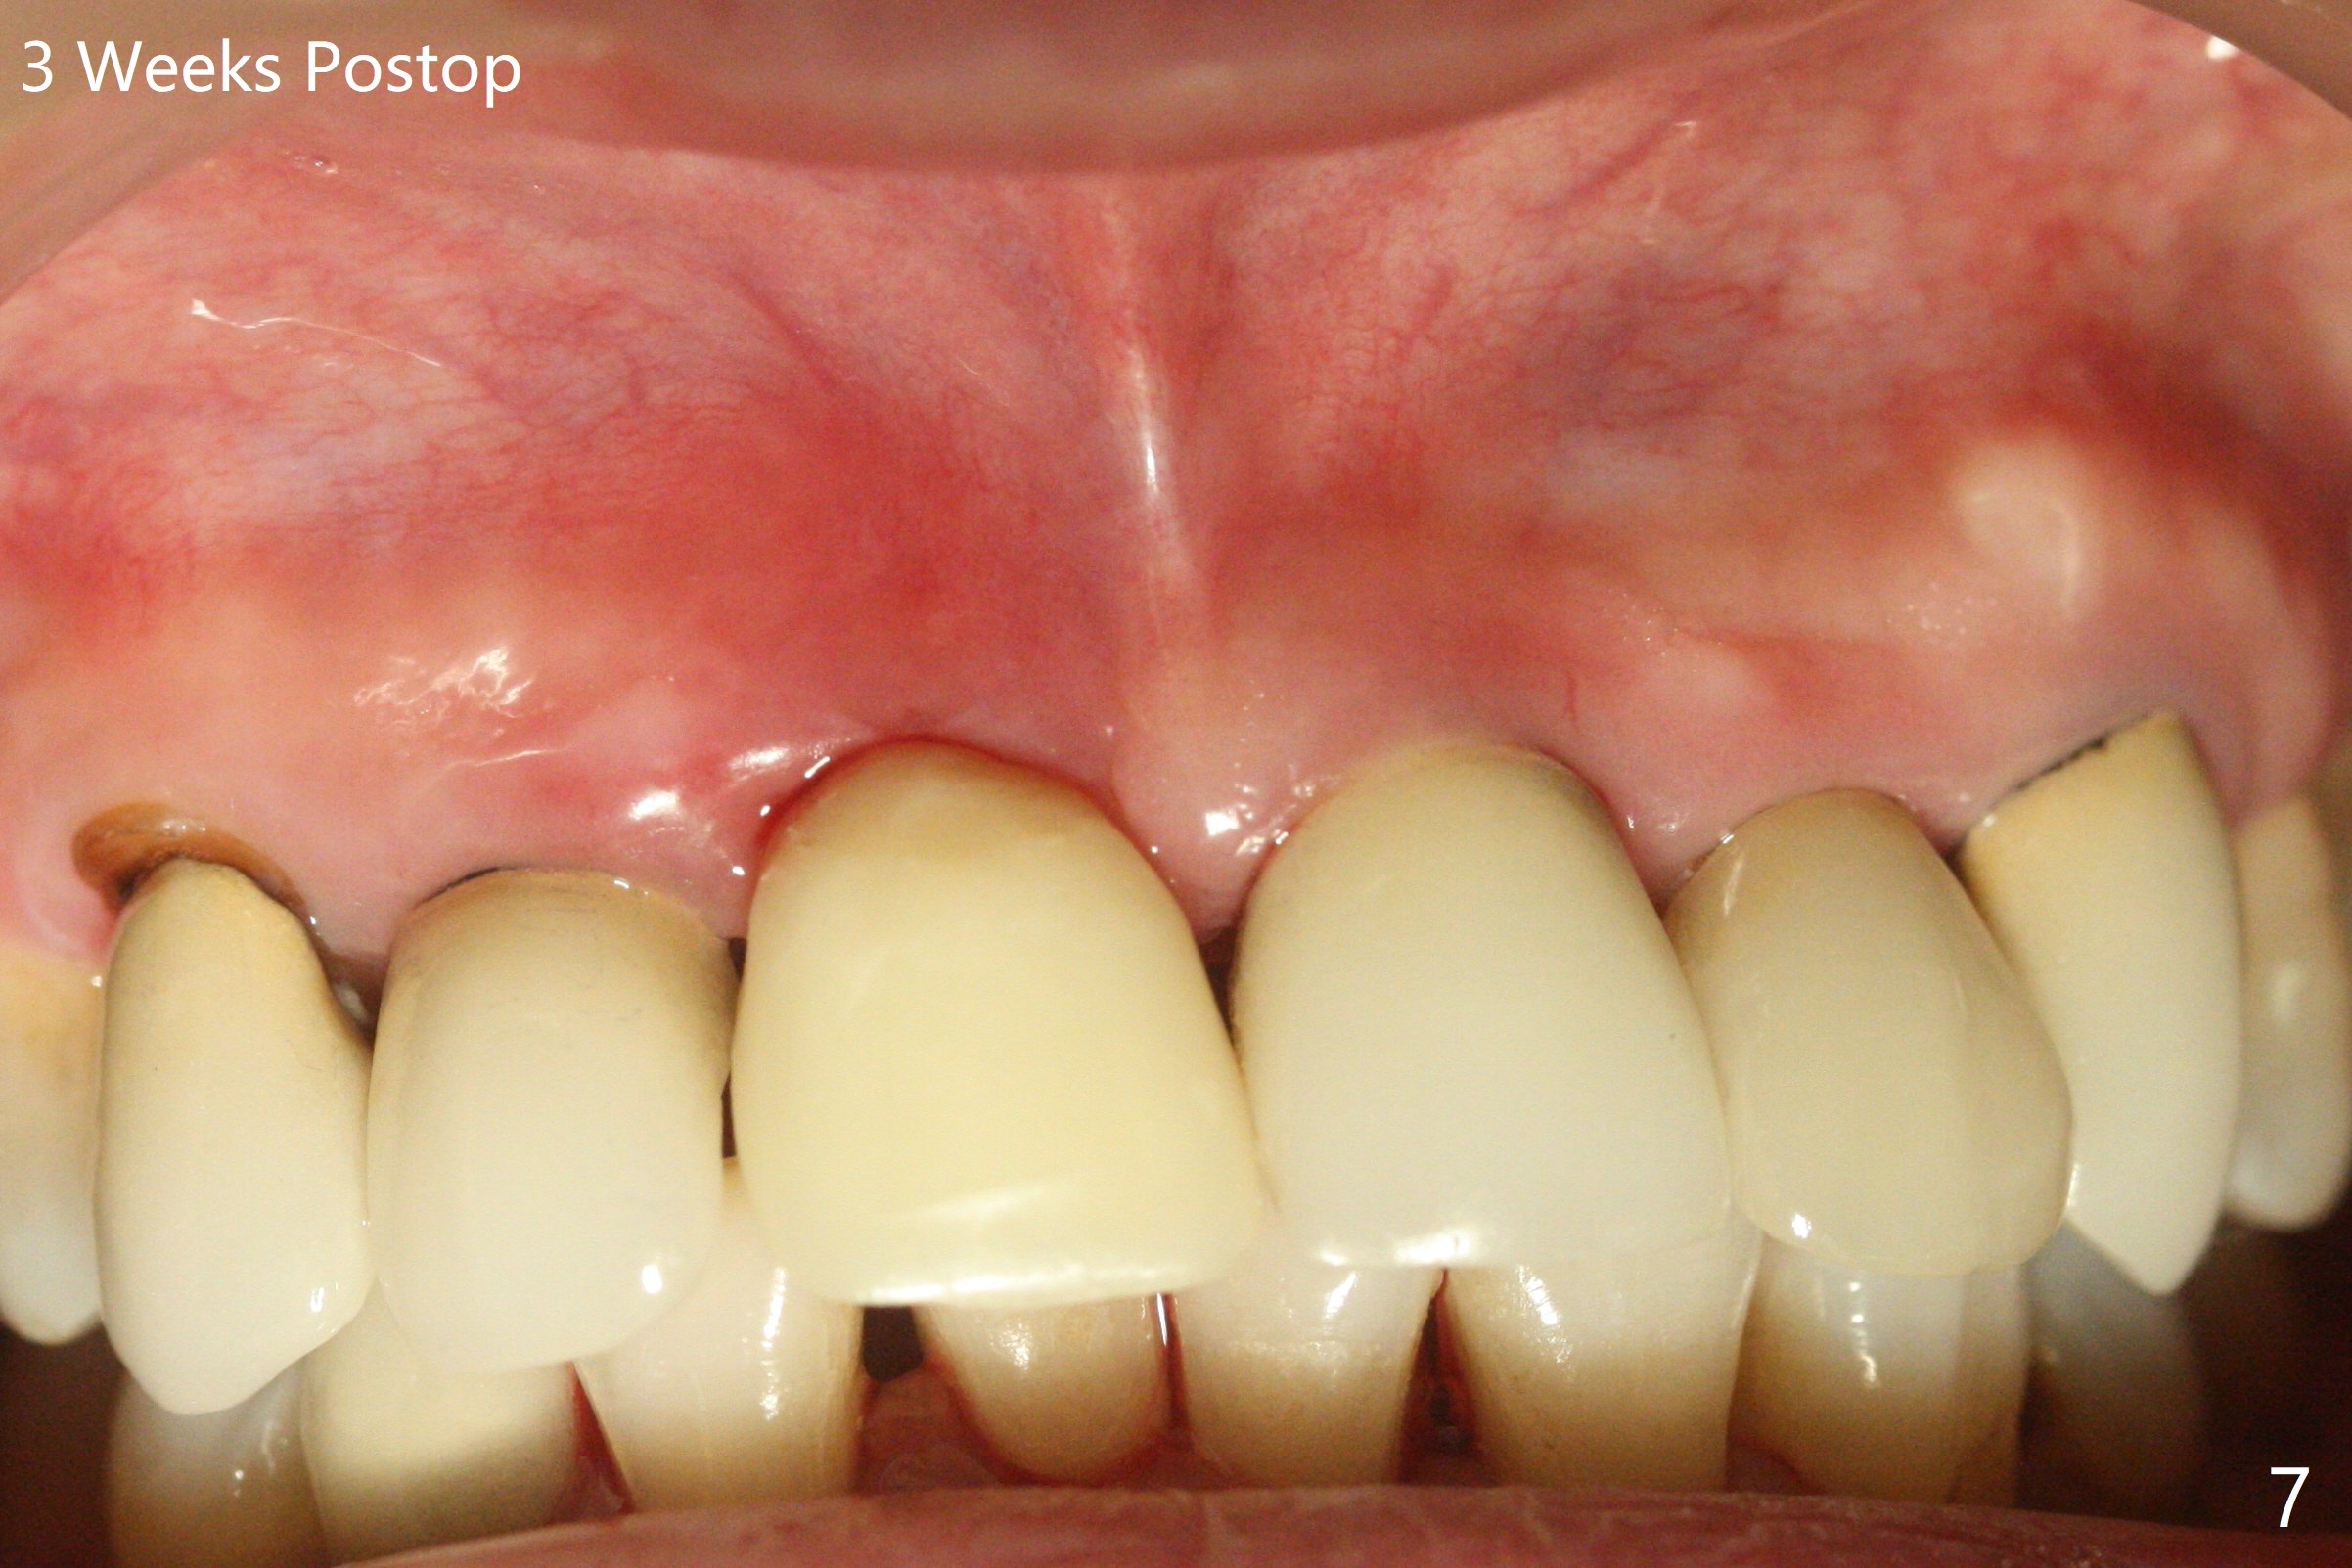

徒手初步钻洞显示方位不对(图一),重新钻洞方位尚可,好像接近鼻底(图二:红线);植入3x11.5毫米一段式植体(图三),3-5个螺纹暴露,植体似乎接近鼻底;旋转植体三趟,植体仿佛卡人鼻底,扭力大约35Ncm,植入粘性骨粉(图四,五:*)前,塞入PRF膜,紧贴颊侧粘膜,促进瘘道愈合。骨粉不仅围绕植体,而且紧贴邻牙牙根(图六(第二轮植骨:overgrafting):<)。病人术后第二周开始使用水牙线,术后三周牙龈健康多了,瘘道消失(图七)。术后六周颊侧骨壁开始塌陷(图八:>),临时牙冠颊侧颈部显得隆起(*)。调整后,牙冠外形改善(图十一至十三),取模前颊侧牙龈缘有可能下降,两个中切牙龈缘可能一致。术后3.5个月骨粉形态(图十四)与术后即刻(图六)有所不同。颊侧牙龈仍红肿轻度触痛(图十五),可能因为临时牙冠不利于局部卫生,所以决定取模制作永久性牙冠。粘固时使用临时胶水,并且涂抗菌素。另外一个可能因素是颊侧骨板薄(图十六:*),细菌感染植体螺纹,永久性牙冠粘固前,拍摄CT(放置cotton roll),必要时,植骨。永久性牙冠远中有缝隙,为了预防病人后悔,使用临时性粘固剂固定(图十七)。Return to No Caries DIO 下一个病例 一段式植体边缘制备 导板与内提升 Xin Wei, DDS, PhD, MS 1st edition 12/22/2020, last revision 06/15/2021